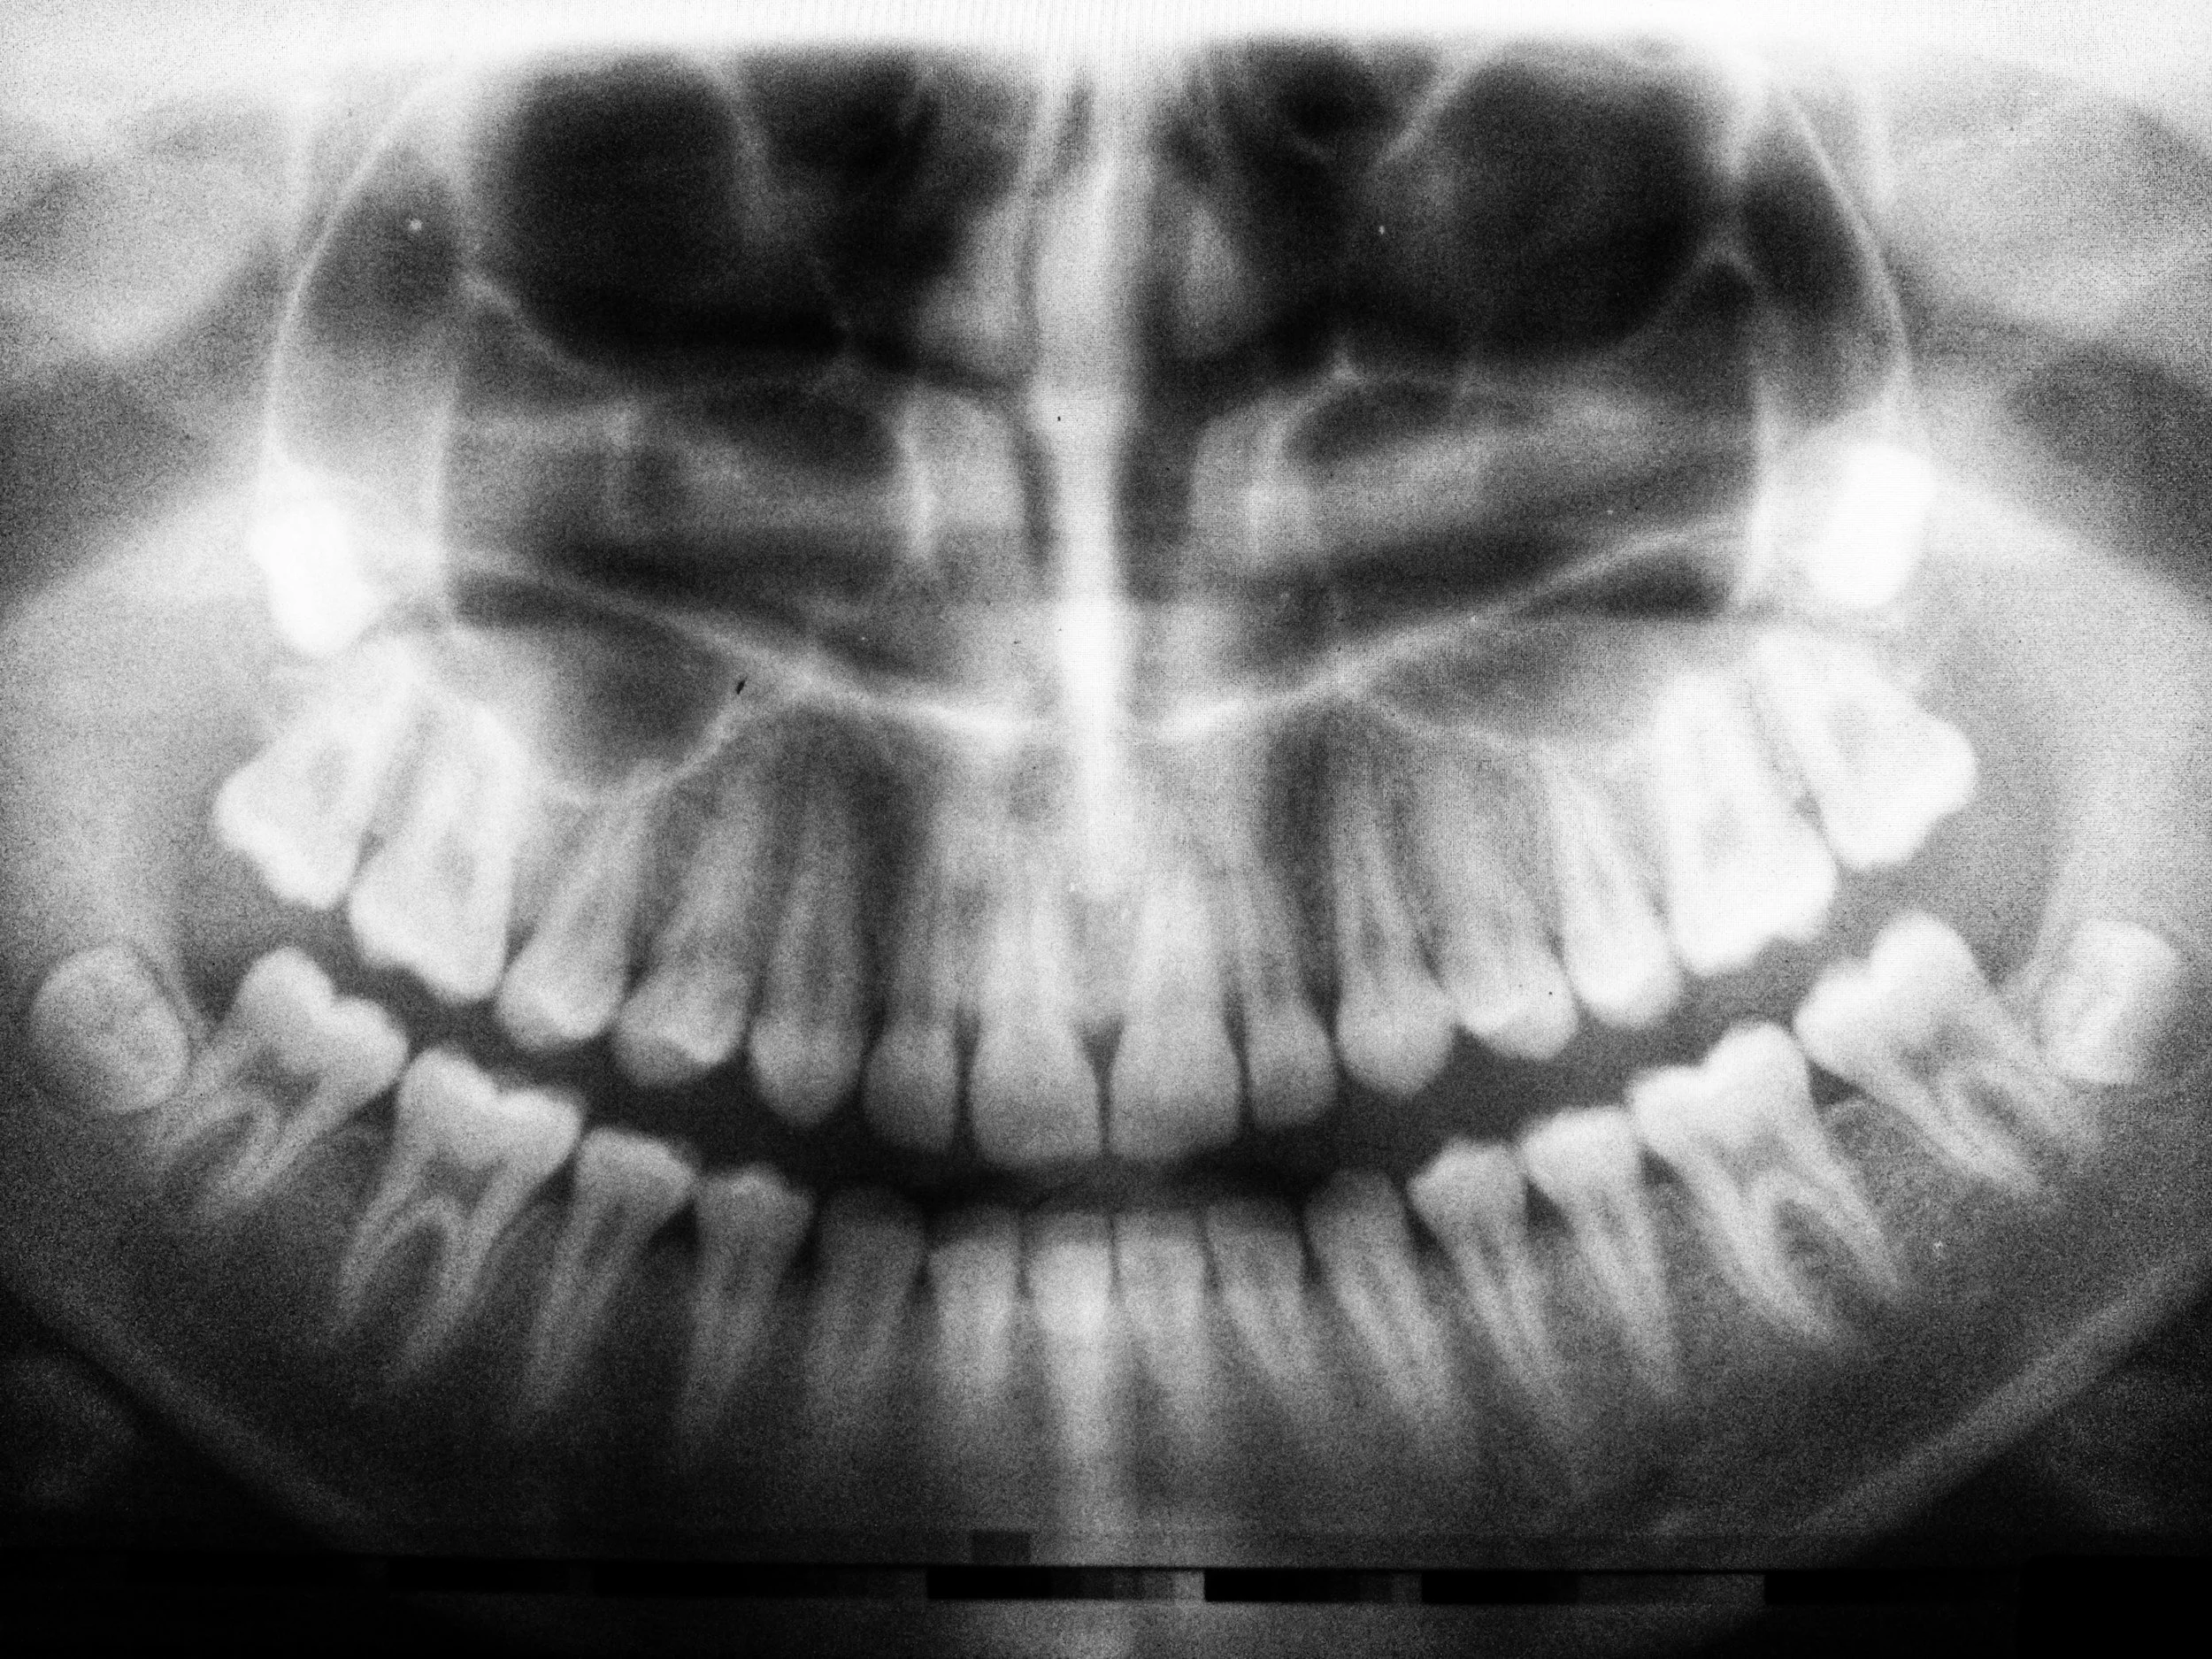

Even more comprehensive X-rays — like panoramic or full-mouth series — are still considered low exposure, especially relative to other common sources in daily life.

Even a full panoramic dental image can be comparable to only a few hours of flight time.